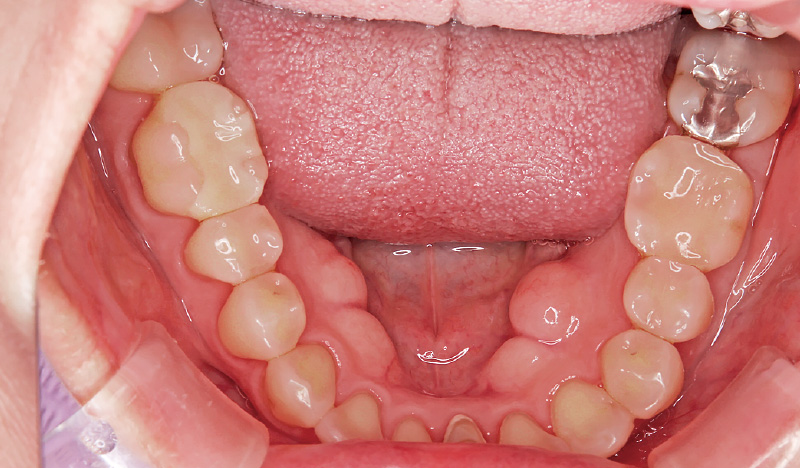

症例2-3 隔壁を形成し、審美性の高いCR充填を行った。(「ルナビューショット」で撮影した動画より抽出) -

症例2-4 現在の口腔内。治療前から途中経過、治療後までを随時撮影し、治療経過の評価や患者さんとのコミュニケーションに活用している。 -